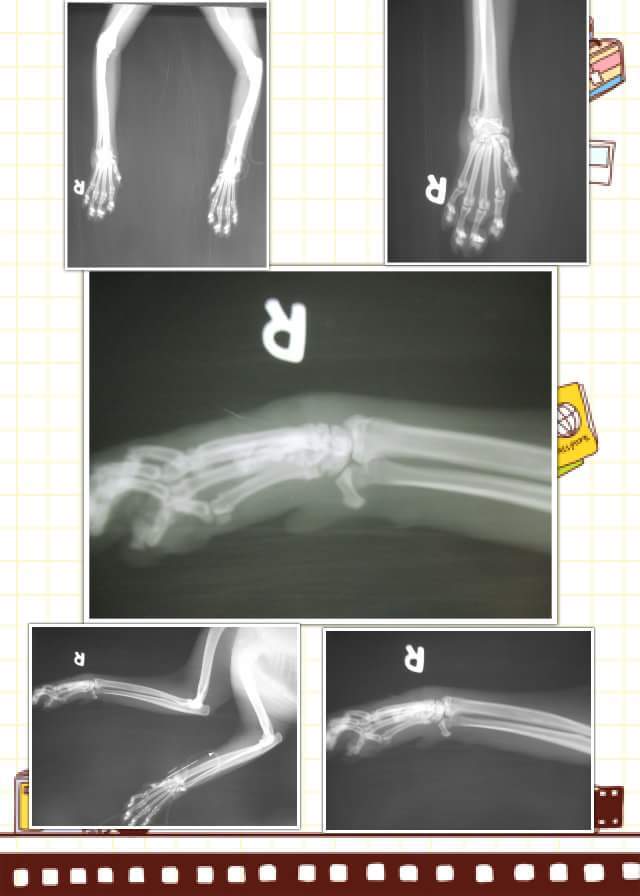

豹豹是我新家餵養區的孩子,每天聽到我來時,都會一邊喵,一邊跑來吃飯,有2天放飯時豹豹沒出現,2天後出現了,但發現他的右前肢受傷了跛腳,無法著地,都用3隻腳行動,擔心是否為車禍骨折,於是補抓帶至醫院檢查。

經醫師檢查結果,豹豹的右腳為蜂窩性組織炎有很大的一個傷口,骨頭並未斷裂或受傷,初步血檢白血球及alkp偏高,貓二合一檢驗,貓愛滋為陽性,醫療費用如下:

5.X光 300* 2 = 600

合計 10400元動物近況說明: 11/2送豹豹去醫院,醫生幫豹豹血檢、照X光發現右前手有一個大洞,蜂窩性組織炎,才導致前手沒法著地,醫生醫生幫豹豹清創並上點滴。11/3去醫院看豹豹食慾,精神都ok。,11/9去看豹豹,豹豹點滴已拆除,目前傷口還是包紮中。11/11去看豹豹傷口有慢慢癒合中。11/18醫生告知豹豹傷口已好,走路也正常了,可以出院了。目前豹豹安置在我這,謝謝協會跟大家和醫生,助理的幫忙,謝謝大家~